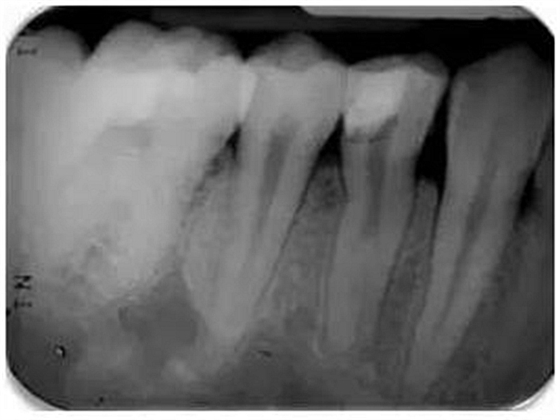

根尖周X線片必須要有最小的失真率和放大倍率,因為任何伸長和透視縮短都會導(dǎo)致根管長度測量的錯誤。對牙根進行仔細的評估是必不可少的,因為可能有畸形牙根(圖1)。在中國患者中發(fā)現(xiàn)C形根管或其他蒙古人種特征的畸形牙根和根管是很常見的。因此,對X線片進行全面評估以確定是否存在額外的牙根或根管是必要的,由此我們可以判斷治療的難度系數(shù)。